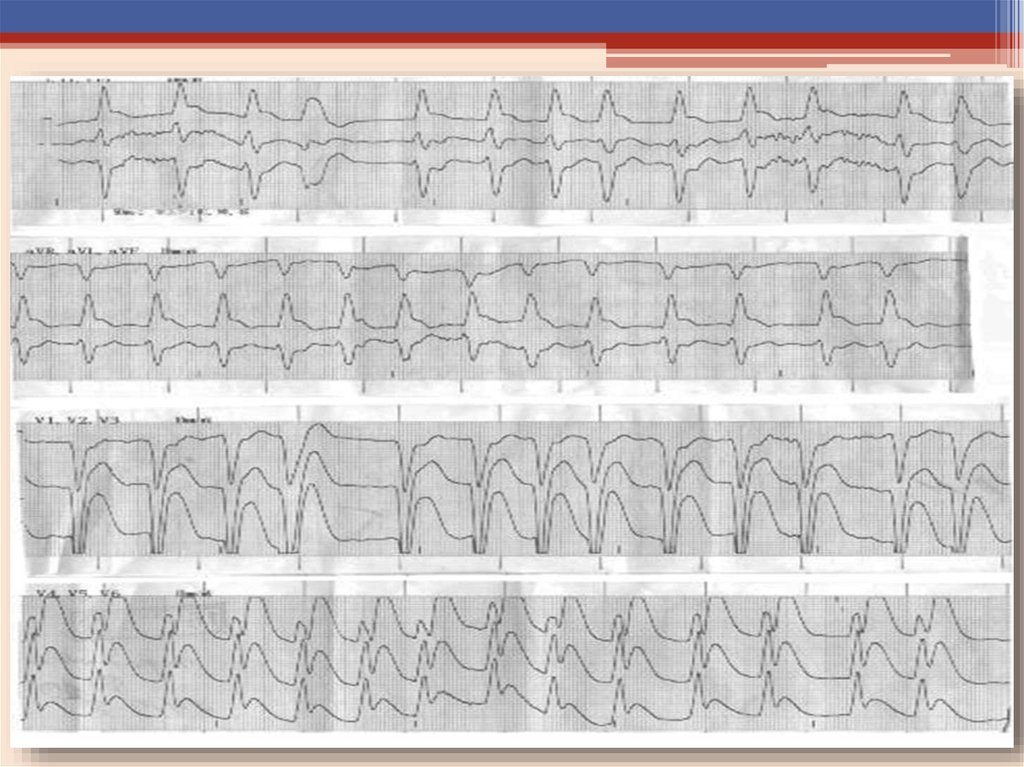

ЭКГ: ЧСС – 63/мин. Синусовая аритмия. Неполная блокада правой ножки пучка Гиса. Синдром

ранней реполяризации желудочков.

СМ-ЭКГ: Эпизод элевации ST ˃2 мм, в V1, V2 и депрессии ST в I, II, AVL с инверсией зубца Т в AVL

на фоне физической нагрузки сопровождающийся болевым синдромом.

Нагрузочная проба положительная. Толерантность к физической нагрузке низкая.